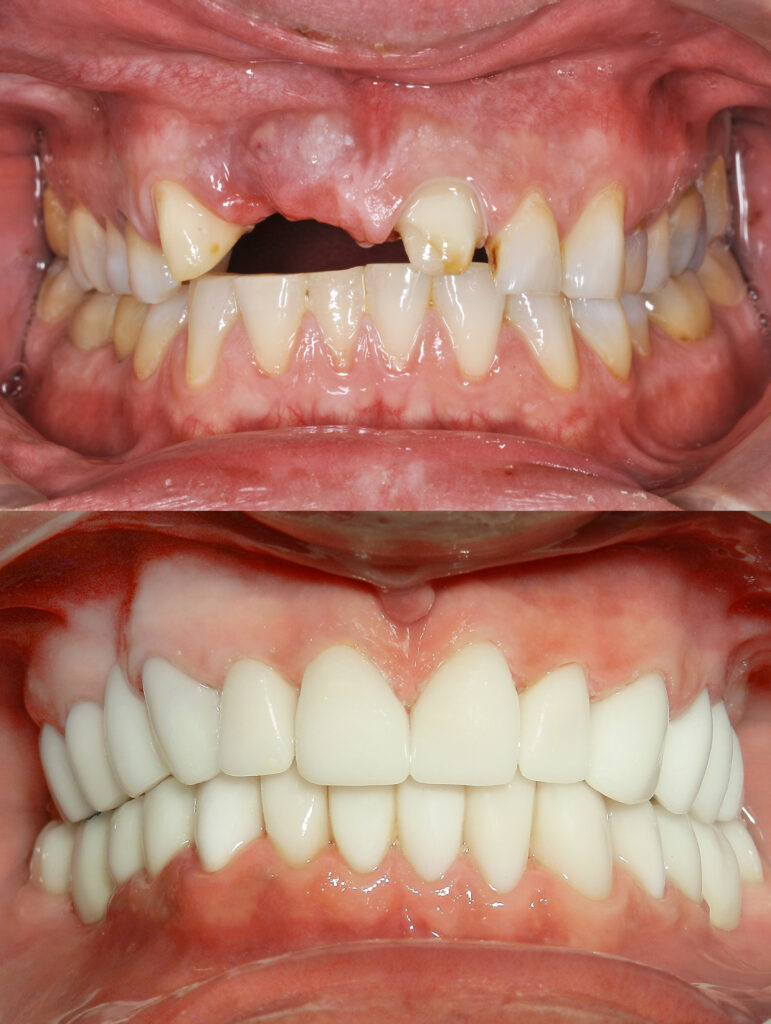

All-on-X Dental Implants

A Full Smile Transformation in Fewer Implants

If you’re missing most or all of your teeth — or struggling with loose dentures — All-on-4 dental implants offer a permanent, stable, and life-changing solution.

At Plaza Dental Care, we restore full smiles using advanced All-on-X technology, giving you fixed teeth that look natural and feel secure.